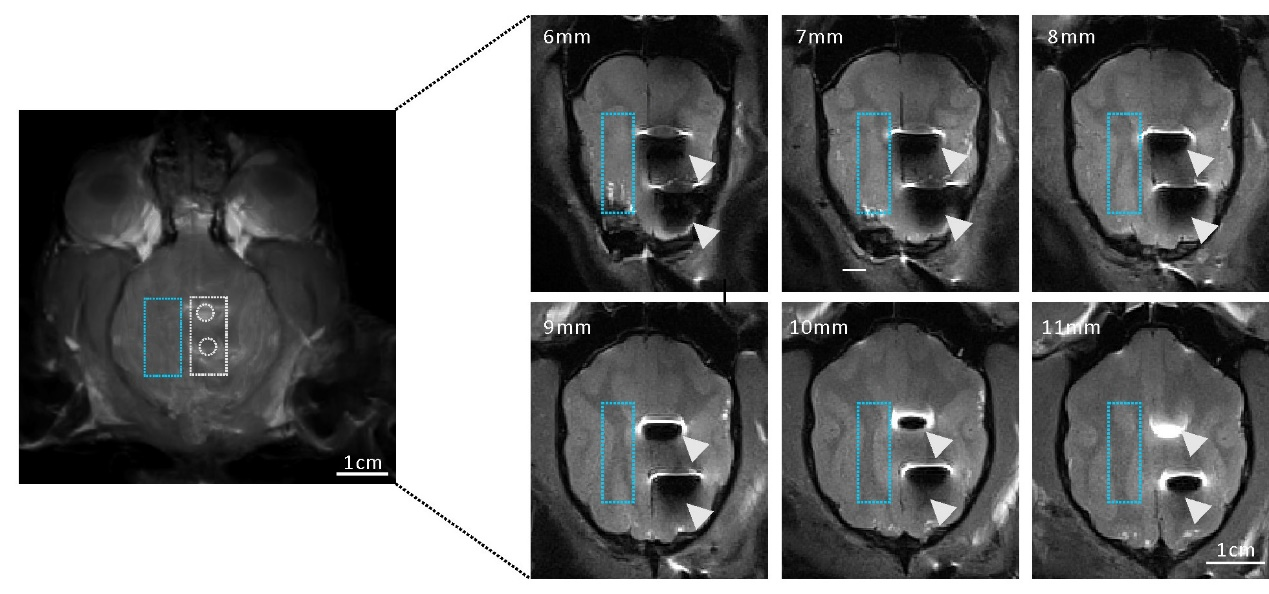

Ӳ�XĤ��Ƥ��늘O��ECoG늘O����һ�N��Ҫ����ӛ䛽ӿڣ��F����ѽ��V�������ڰd�B���λ�����R�����x֫���R�����Լ������I�򡣵�����Խ������錧늲��ϵ�ECoG늘O���������Բ�O�דp���X���棻߀���䲻͸�������������ECoG늘O�Ķ�ģ�B���ã���͹��z���W���p���ӳ����MRI����ȣ���

���˽�Q���φ��}���㽭��W���ƽ��ڈF��c�㽭��W�������о��T�Լ������W�i־��Ժʿ�F꠺����_�l��һ�N����PVA-ACSFˮ���z늘O��ԓ늘O�������W�����c���W���|���X�M���߶����ƣ���͸�����Լ��˴ż����Ե����c����˾��ЏV�����R���Ϳ��Б��Ãrֵ��

�D����ˮ���z늘Oӛ䛵������̖�|���ͽ���늘O�߶�����

ԓPVA-ACSFˮ���z늘O��ӛ䛵����и߶ȕr�շֱ��ʵĸ��|��Ƥ�������̖��

�D�壬ˮ���zƤ��늘O��Ӱ�MRI���񣨲������ҷ��Ľ���늘O�a���ܴ�Ă�Ӱ��

������PVA-ACSFˮ���z�Ļ��W���ɺ��X�M���߶������ԣ��@ʾˮ���z늘O��Ӱ�MRI�˴ų��񡣾C���@�N���͵�PVA-ACSFˮ���z늘O���H�о޴���R�����Ý��������ĸ߶�͸�����Լ��˴ż����Ե����cʹ�����Ժ͹�W���񣬺˴ų����Լ����z���W�����M���g����ϣ�����A�о��ṩ������x���c�����ԡ����ĵĵ�һ���ߞ��㽭��W�t�WԺ��ʿ������������ͬ��һ���ߞ��㽭��W�t�WԺ��ʿ���������͹����W��ʿ��ʢ����㽭��W���x�WԺ��ʿ�������鱾����������Ҫؕ�I���㽭��W�t�WԺ�������ڡ��㽭��Wϵ�y���c�J֪�ƌW�о����������о��T�Լ������W�i־�����ڞ鱾�ĵĹ�ͬͨӍ���ߡ�ԓ����Ҳ���^�����F�2019����Extreme Mechanics Letters�l��������ʽˮ���z늘O���m�����о���